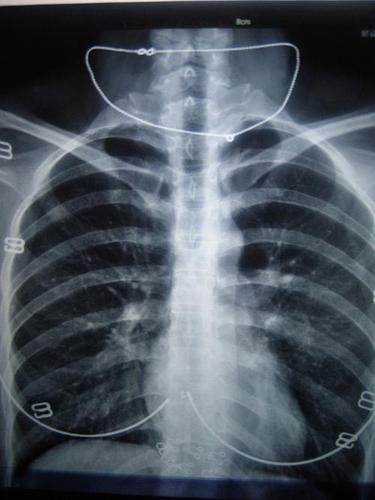

帮看下这个胸片看是什么病谢谢

28岁女 图一是胸片 图二是医生画的小圈那个地方是觉得有问题的地方

求高手看一胸片

有学医的同学看下x胸片嘛!